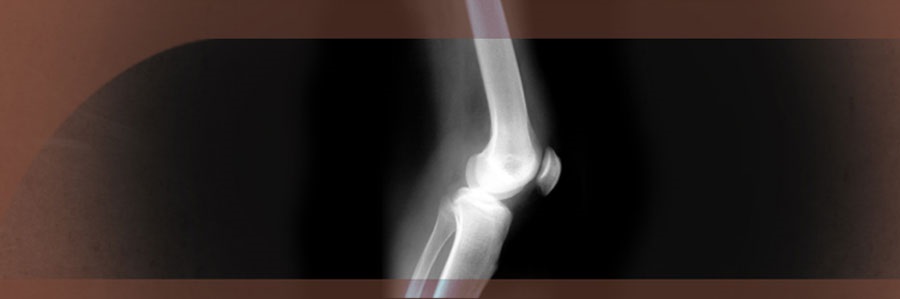

هنگامی که به آسیب‌های ورزشی پرداخته می‌شود، شانه و زانو نواحی از بدن هستند که بیشترین احتمال آسیب را دارند. زانو یکی از پیچیده‌ترین مفاصل بدن است. از آنجا که در بیشتر ورزش‌ها تنش زیادی بر مفصل زانو وارد می‌شود، زانو یکی از شایع‌ترین قسمت‌هایی است که تحت آسیب‌های ورزشی قرار می‌گیرد.

آسیب‌های زانو اغلب شامل پارگی یکی از چهار رباط اصلی است که استخوان‌ها را در محل مفصل زانو به یکدیگر متصل می‌کنند. شایع‌ترین آسیب، پارگی رباط صلیبی قدامی (ACL) می‌باشد.

گاهی پارگی ACL به همراه پارگی یکی دیگر از چهار رباط اصلی زانو نظیر MCL یا رباط طرفی داخلی رخ می‌دهد به خصوص هنگامی که آسیب ناشی از برخورد باشد. صدمه به ACL معمولاً به دلیل تابیده شدن یا حرکت چرخش روی پاشنه رخ می‌دهد.